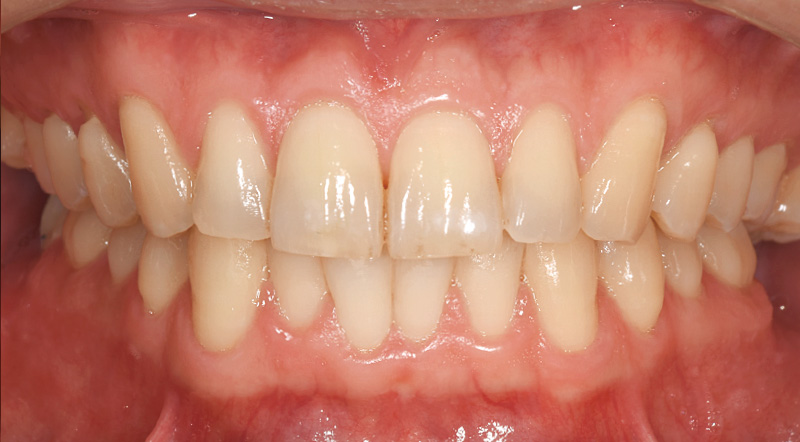

●症例1:50代男性

月に一度来院し、プロフェッショナルケアを継続されていました。セルフケアについては、どれだけ指導しても手磨きではモチベーションが上がらず磨き残しが多い状態で、1日40本の喫煙による着色も見られました。そんな中、インプラント治療後にインプラント周囲炎のリスクが高まり、セルフケアが不可欠になったことから、「ソニッケアー6100プロフェッショナル」(以下:ソニッケアー6100)の導入を提案。「歯磨きが楽になる」という利点を伝えながら使い方を指導したところ、思いのほか前向きに受け入れてくださり、導入後2週間でプラークや着色が大幅に減少するという顕著な改善がありました。患者さん自身も効果を実感し、セルフケアに対するモチベーションもぐんと上がった様子でした。

![[写真] 「ソニッケアー6100」使用前。写真右:使用から2週間後の状態](/academic/dentalmagazine/wp-content/uploads/sites/2/2026/04//196-12_photo06.jpg)

症例1-6 写真左:「ソニッケアー6100」使用前。写真右:使用から2週間後の状態。着色が大幅に減少していることがわかる。